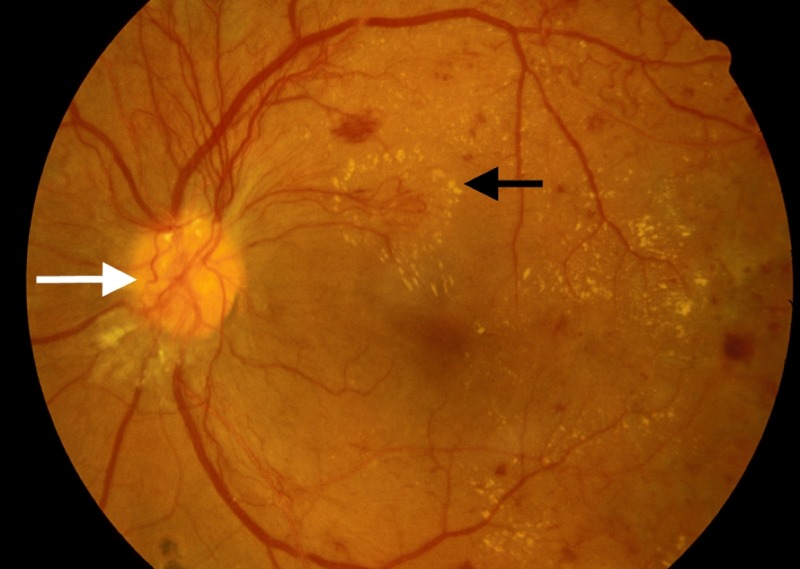

Medical Imaging and Diagnosis